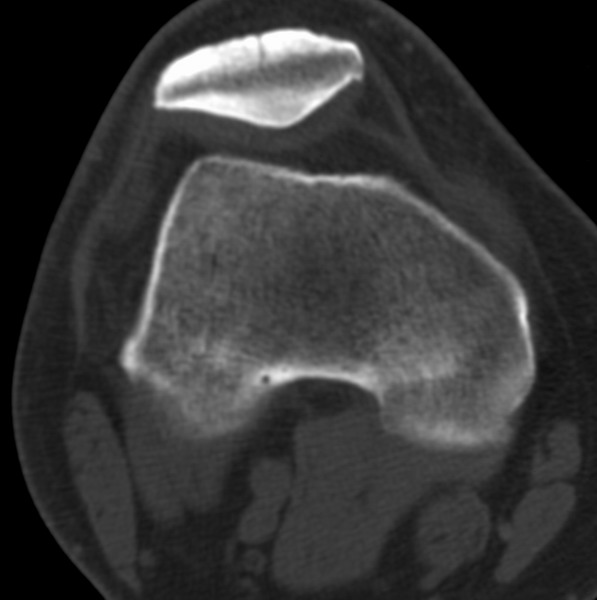

标题: CT21959:骨肿瘤请会诊。

右侧膝关节疼痛一月

男、48

股骨下段、胫骨上段。

1、股骨干骺端病变考虑干骺端纤维性皮质缺损愈后(非骨化性纤维瘤)改变,胫骨近端内生骨瘤(或干骺端纤维性皮质缺损愈后改变);

2、骨关节炎,骨质增生,股骨外侧髁退变性囊肿(关节面软骨下囊肿);

1、股骨干骺端病变考虑干骺端纤维性皮质缺损愈后(非骨化性纤维瘤)改变,胫骨近端内生骨瘤;